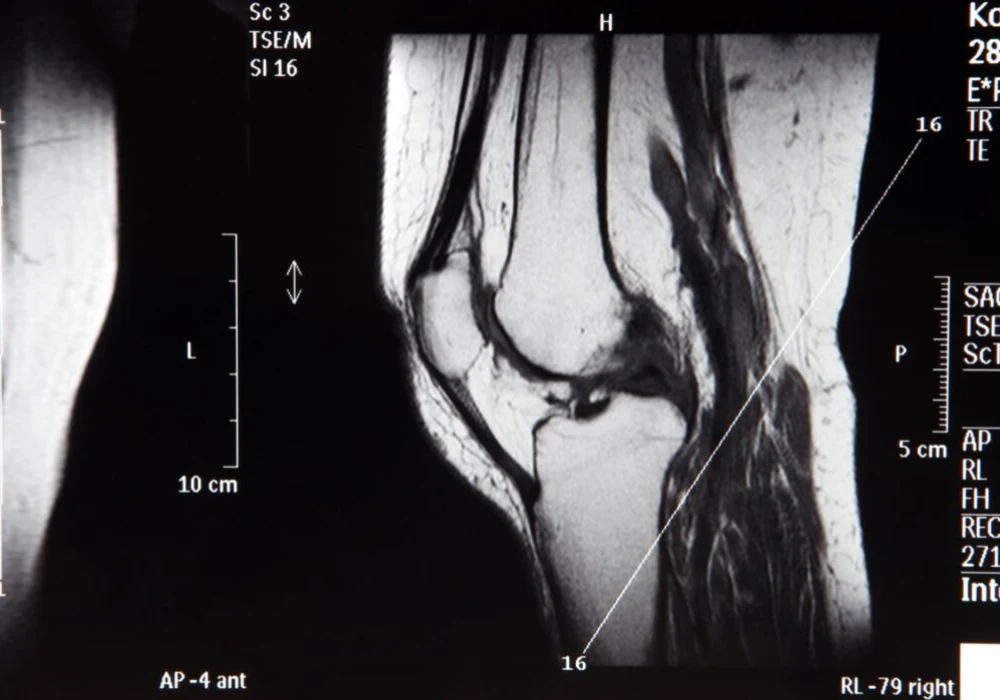

Rising MRI volumes and increasingly complex examinations continue to pressure radiology services. Responding to this demand, researchers developed a deep learning (DL) model to analyse routine knee MRI and assessed its value for resident radiologists. The model targets 23 conditions across cartilage, menisci, bone marrow, ligaments and other soft tissues, reflecting typical clinical reporting needs. Training and internal evaluation used 3121 studies from a high-volume radiologic practice, with external testing on 458 studies from a university hospital. Performance was quantified with area under the receiver operating characteristic curve (AUC), sensitivity and specificity, and a controlled reader study measured the model’s impact on accuracy, efficiency and agreement among residents. Results indicate that multi-condition assistance can raise sensitivity, stabilise agreement and shorten reading times, while highlighting the importance of condition-level performance transparency.

The model was designed around non-contrast routine knee MRI protocols comprising axial, coronal and sagittal proton density-weighted fat-saturated sequences, plus a sagittal T1-weighted sequence. Images underwent histogram normalisation, intensity clipping and rescaling, then were resized to 256 × 256 pixels with 32 slices to standardise inputs. The architecture adapted a multi-sequence transformer approach, using a ResNet18 backbone enhanced with residual 3D blocks to encode each slice as a context-aware token before transformer-based classification. Labels for 23 binary (and some ternary) condition categories were derived from clinical reports using a structured template and multi-step quality control by board-certified radiologists, aiming to balance annotation scale and reliability.